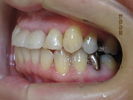

60代男性

右上に入れ歯を作ったが噛めず右で食事できないため来院。

2本インプラントをしました。

手前の銀色のかぶせも白いかぶせにかえました。

食事しやすくなったと喜ばれました。

治療前 |

治療後 |

![]() |

| 治療前 | 治療後 |